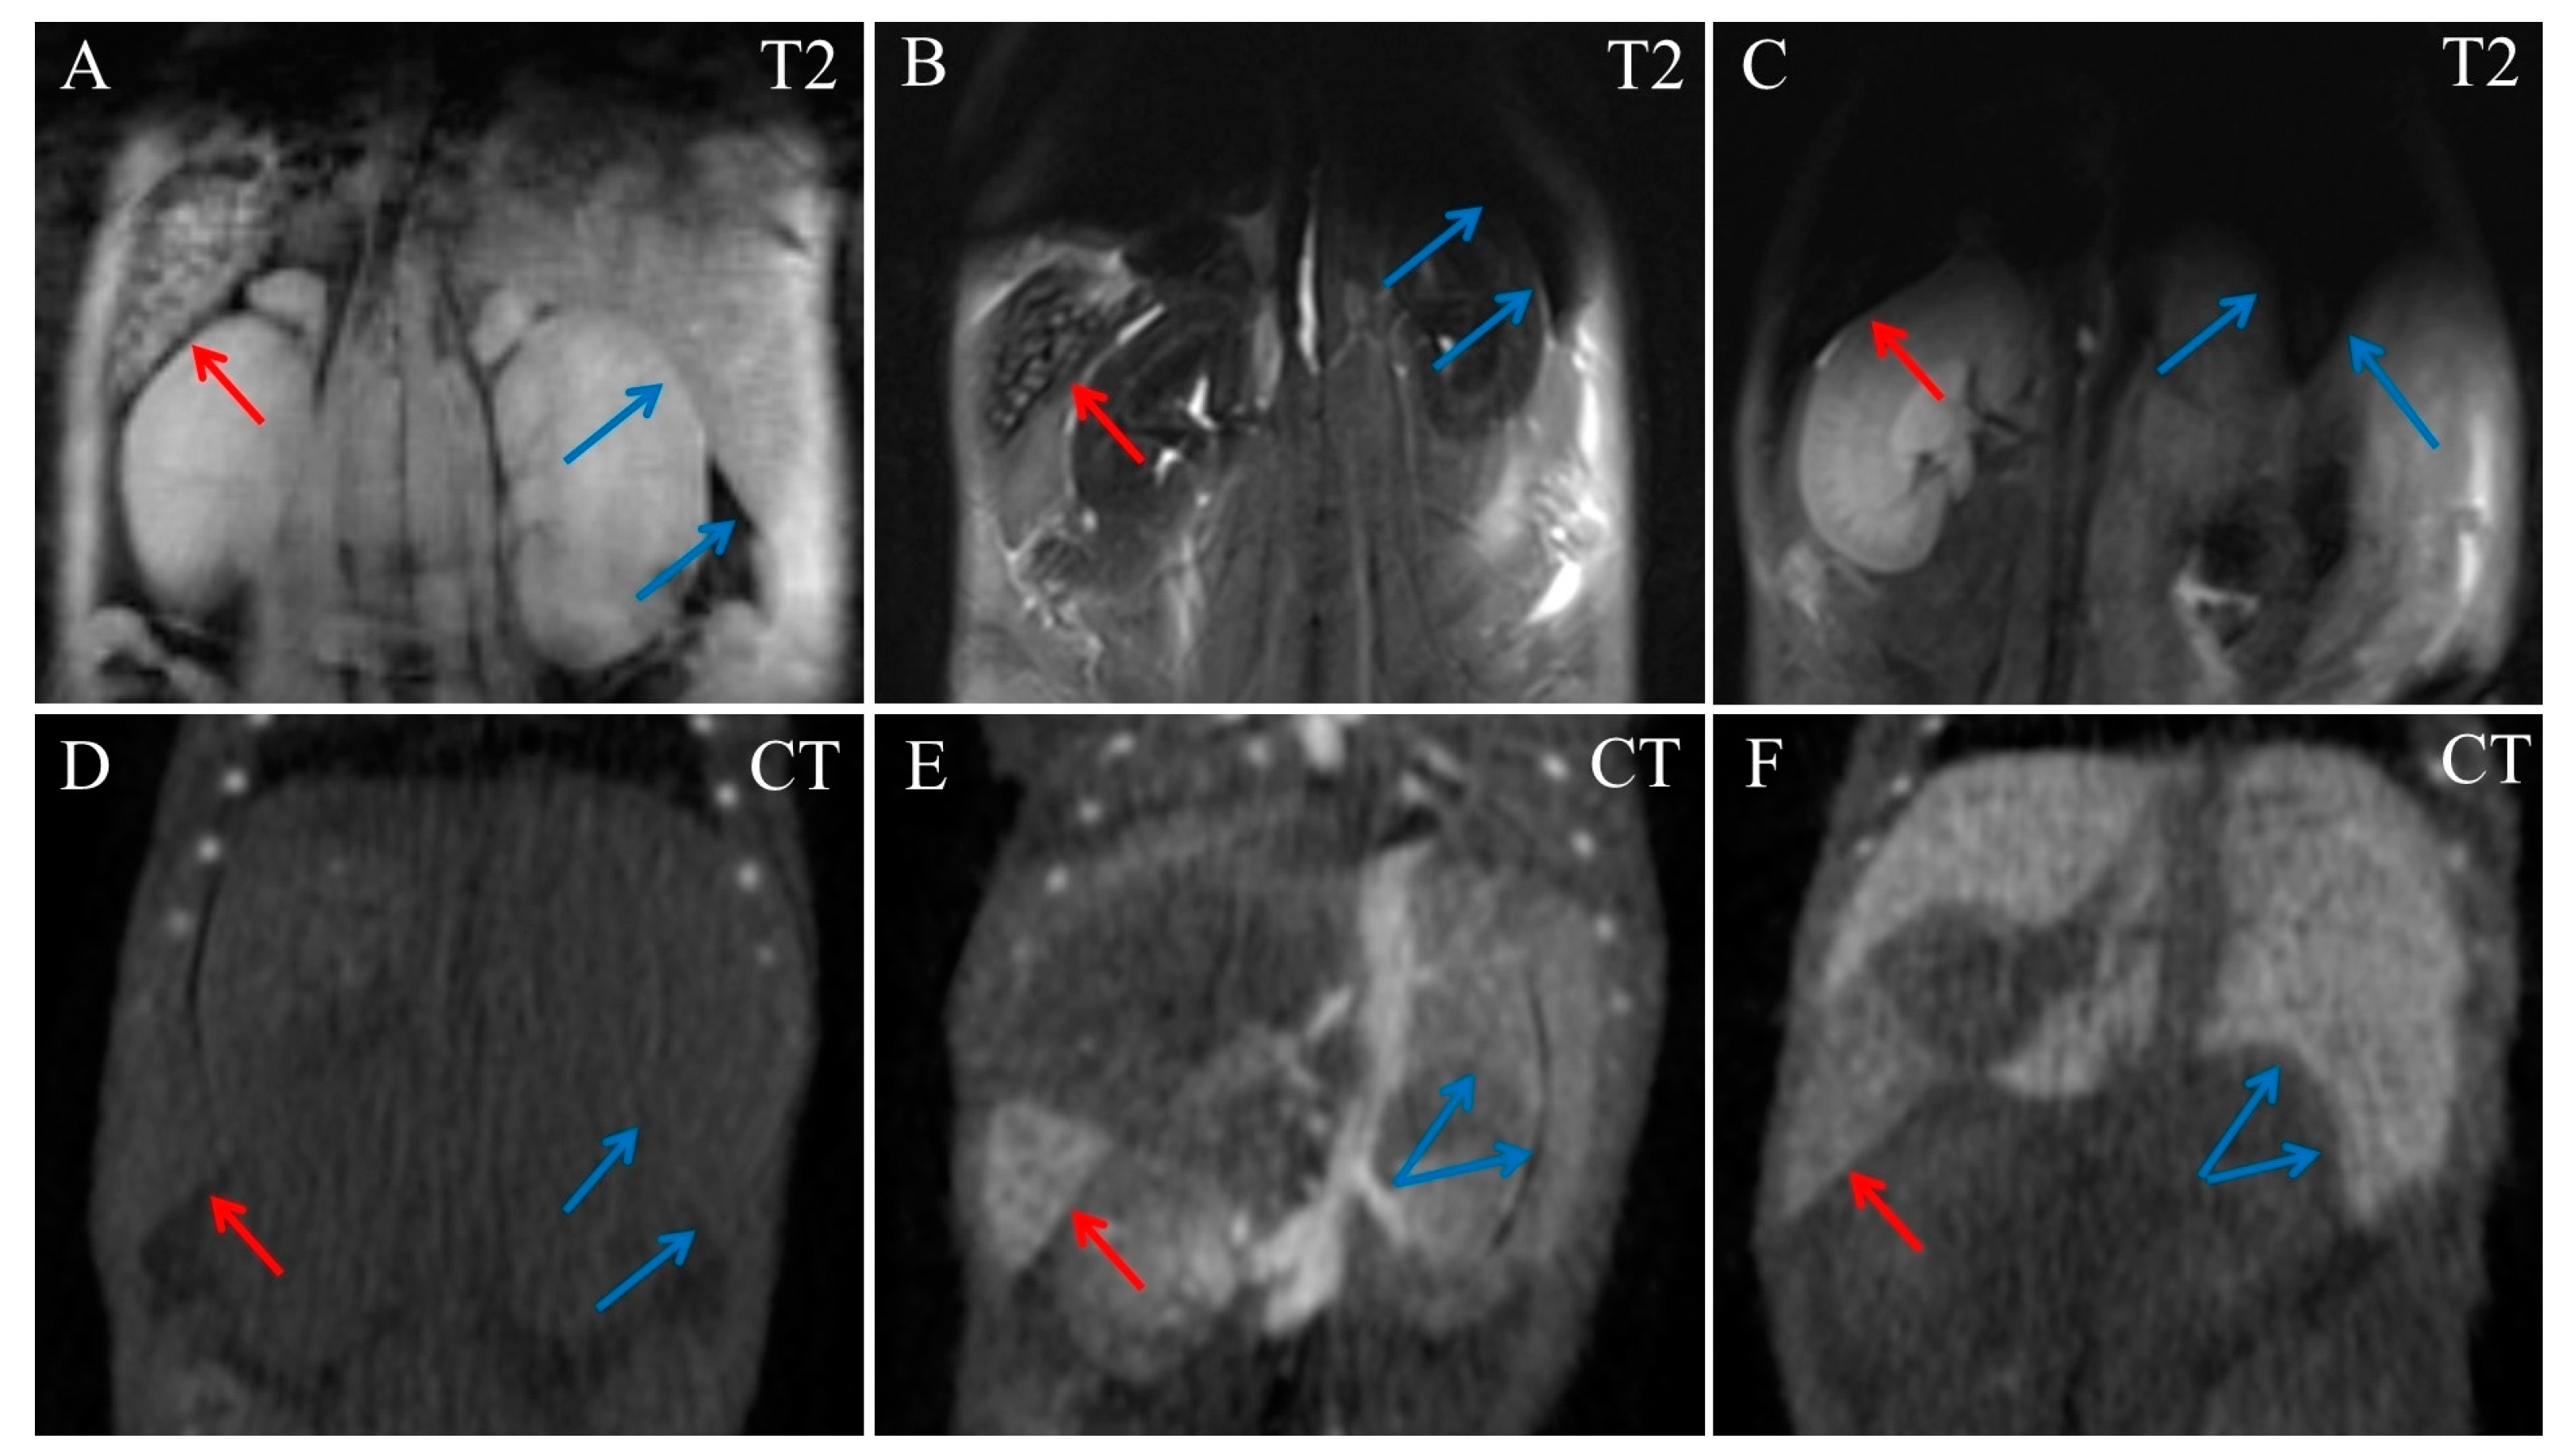

2. Results